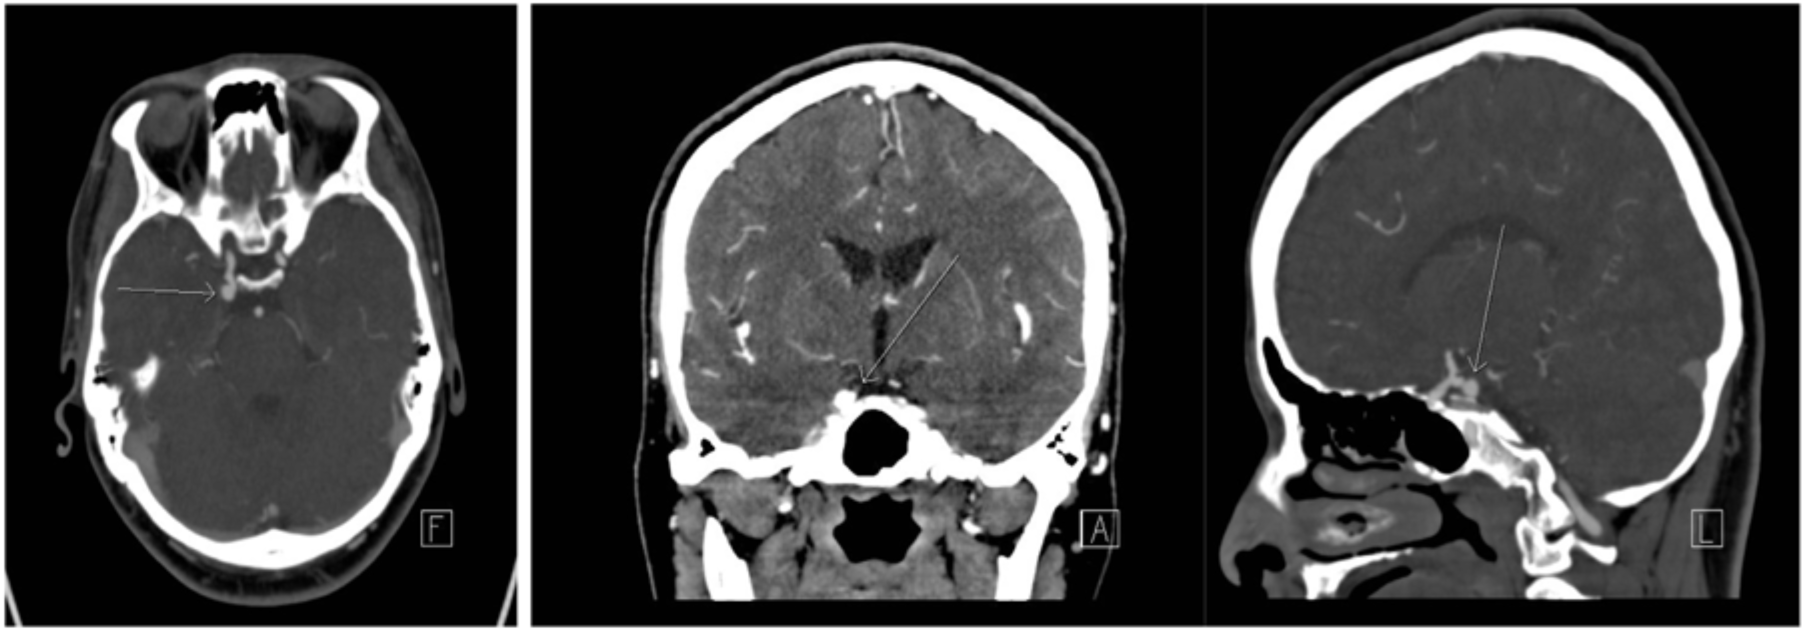

After 10 months, the patient presented again to hospital with a 1-week history of thunderclap headache followed by right-sided ptosis and inferolateral deviation of the right eye. Physical examination demonstrated a complete right cranial nerve III palsy. Cardiovascular examination demonstrated a 2/6 systolic ejection murmur at the left upper sternal border, new from previous, but otherwise normal findings. MRI of the brain demonstrated no change from previous or evidence of acute infarct. CTA of the head and neck demonstrated a right posterior communicating artery (Pcomm) aneurysm (Figure 1), which was very subtle in retrospective review of the CTA at initial presentation, 10 months prior. Neurosurgical consultation led to right Pcomm aneurysm clipping. TTE was subsequently performed to investigate potential causes of embolization and revealed a left atrial mass (Figure 2). CT of the chest was done to further characterize the mass, suggesting a diagnosis of atrial myxoma. After several weeks, the patient underwent open-heart surgery for mass resection. Pathology confirmed the diagnosis of atrial myxoma. Further history did not reveal personal or family history of aneurysms or disorders associated with cerebral aneurysm formation, such as Ehlers–Danlos syndrome or autosomal dominant polycystic kidney disease. The patient was discharged having experienced no recurrent embolic phenomena.

Figure 1: CTA for the head reveals right posterior communicating artery aneurysm.